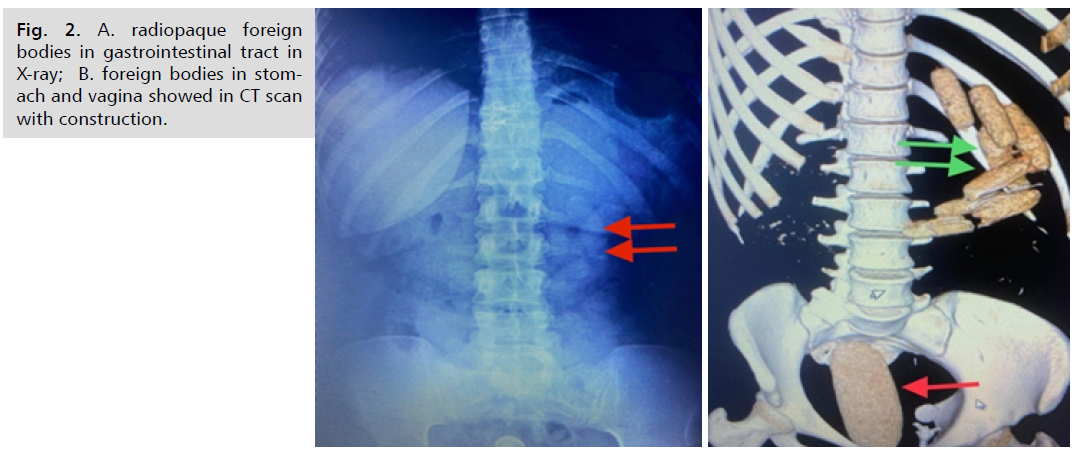

A 29-year-old female was brought to hospital by airport security per-sonnel with suspicion of foreign body ingestion. Suspect admitted ingestion of 8 cocaine packets and put some packets in the vagina. On examination, the suspect was a febrile; her abdomen was soft and lax. Abdominal radiographs (Fig.2.). show radiopaque foreign bodies in gastrointestinal tract and show no signs of bowel obstruction or perforation. Non contrast abdominal CT (Fig. 2.). Reveals multiple spherical and cylindrical shaped hypodense, almost same sized foreign bodies in stomach and vagina. Suspect was given lactulose and passed some packets, with auto remove of packet at the vagina.

universal-surgery-radiopaque

Fig. 2. A. radiopaque foreign bodies in gastrointestinal tract in X-ray; B. foreign bodies in stomach and vagina showed in CT scan with construction.

Endoscopy is used to extract the rest of packets. CT followup revealed no remaining packets in abdomen or pelvis. Suspect was generally well, vitally stable. The patient was then discharged in the custody of the police